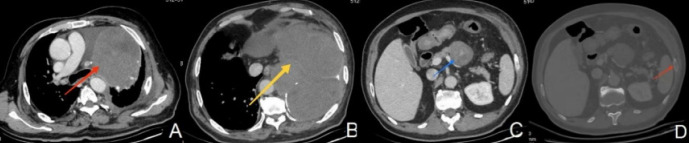

原发性肺脂肪肉瘤极为罕见。迄今为止,在英国文献中仅报道了24例。在此,我们报告一例高分化肺脂肪肉瘤,在正电子发射断层扫描/计算机断层扫描(CT)和增强CT上被误诊为畸胎瘤。行根治性手术,左上肺叶切除及纵隔淋巴结清扫。患者术后33个月出现复发和远处转移。在撰写本报告时,患者还活着(术后36个月)。据我们所知,这是第一例肺高分化脂肪肉瘤的报告。

Primary liposarcoma of the lung is extremely rare. To date, only 24 cases have been reported in the English literature. Herein, we present a case of well-differentiated pulmonary liposarcoma that was misdiagnosed as teratoma on positron emission tomography/computed tomography (CT) and contrast-enhanced CT. Radical surgery with left superior lobectomy and mediastinal lymph node dissection were performed. The patient experienced recurrence and distant metastases 33 months after surgery. He was alive at the time of writing this report (36 months postoperatively). To our knowledge, this is the first case report of pulmonary well-differentiated liposarcoma.